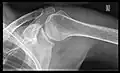

Conventional x-rays and ultrasonography are the primary tools used to confirm a diagnosis of injuries sustained to the rotator cuff. For extended clinical questions, imaging through Magnetic Resonance with or without intraarticular contrast agent is indicated.

Hodler et al. recommend starting scanning with conventional x-rays taken from at least two planes, since this method gives a wide first impression and even has the chance of exposing any frequent shoulder pathologies, i.e., decompensated rotator cuff tears, tendinitis calcarea, dislocations, fractures, usures, and/or osteophytes. Furthermore, x-rays are required for the planning of an optimal CT or MR image.[25]

X-ray

Projectional radiography views of the shoulder include:

Transaxillary projection

The arm should be abducted 80 to 100 degrees. This method reveals:[26]

• The horizontal alignment of the humerus head in respect to the socket and the lateral clavicle in respect to the acromion

• Lesions of the anterior and posterior socket border, or of the tuberculum minus

• The eventual non-closure of the acromial apophysis

• The coraco-humeral interval

Y-projection

The lateral contour of the shoulder should be positioned in front of the film in a way that the longitudinal axis of the scapula continues parallel to the path of the rays. This method reveals:[26]

• The horizontal centralization of the humerus head and socket

• The osseous margins of the coraco-acromial arch and hence the supraspinatus outlet canal

• The shape of the acromion

This projection has a low tolerance for errors and, accordingly, needs proper execution.[26] The Y-projection can be traced back to Wijnblath’s 1933 published cavitas-en-face projection.[27]